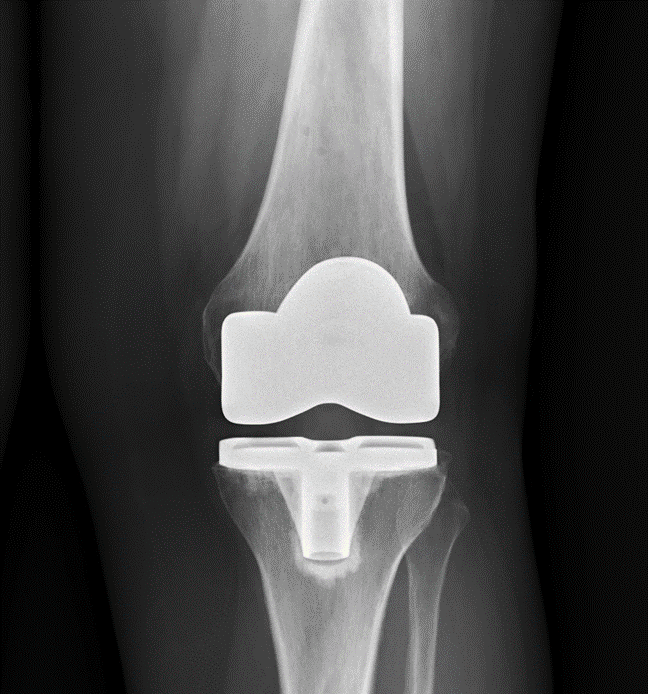

Knee Replacement is a common orthopaedic procedure and is used primarily to treat knee arthritis and cartilage damage of all causes. Knee replacement surgery is now more technologically advanced and utilities assistance from computer navigation and robotic interventions. The Surgery involves removal of arthritic bone surfaces and replacement with metal and plastic leading to improved pain and function in the large majority of patients.

Damage to the knee that is likely to benefit from Knee Replacement surgery is usually diagnosed both clinically, with pain, stiffness and swelling of the knee, and with x-rays. Occasionally an MRI may assist in the diagnosis of Knee Arthritis.

The goals of knee replacement surgery are to reduce pain, increase mobility and function and to restore alignment to limbs with preoperative deformity.